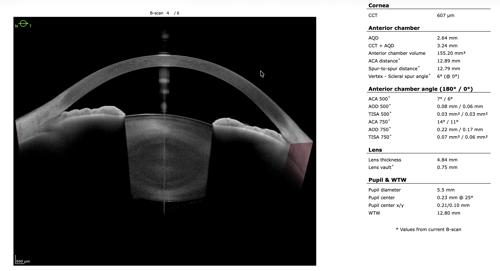

To refine surgical candidacy, anterior segment imaging was performed using the Heidelberg ANTERION SS-OCT. High-resolution imaging clearly demonstrated the following:

- A visually clear crystalline lens, not meeting criteria for cataract extraction

- Markedly narrow angles at iris insertion

- Angle measurements in the single-digit degrees